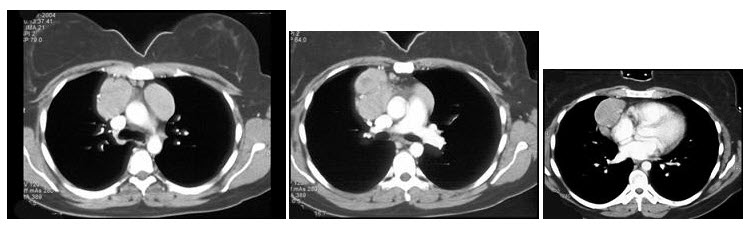

女,27岁,双侧颈部淋巴结肿大,PPD(-),结合CT图像,最可能的诊断是()

A、心包囊肿

B、淋巴瘤

C、淋巴结核

D、转移性淋巴结肿大

E、结节病

B